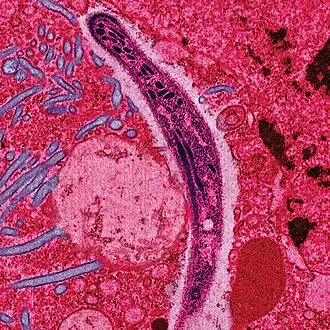

Ветеринарная паразитология — раздел ветеринарии, изучающий паразитов животных и вызываемые ими заболевания и патологические состояния, способы профилактики заражения, способы лечения заражённого или заболевшего животного. Медицинская паразитология — раздел медицины, изучающий паразитов человека и вызываемые ими заболевания и патологические состояния, способы профилактики заражения, способы лечения заражённого или заболевшего человека. Интересная статьяГлистогонные средства, Противоглистные средства (лат. anthelmintica vermifuga) — общее название лекарственных веществ, служащих для выведения гельминтов (глистов) из организма. Противоглистные препараты делятся на три группы в зависимости от класса гельминтов, на которые воздействуют: для лечения нематодозов, цестодозов, трематодозов. Интересное изображение![]() Новые статьи